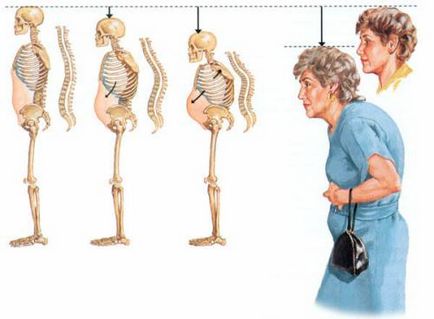

Mivel a ék törések deformációja szervek vezet zavar a testtartási deformáció a gerinc, csökkentik az emberi növekedést. A leggyakoribb megnyilvánulása ék deformáció a csigolyák a megjelenése a púp a háti gerinc (erősített háti kyphosis).

Egy tipikus változás testtartás csontritkulás, amely az úgynevezett „púp arisztokrata”

- progresszív csökkenése a növekedés;

- fejlesztés görnyed;

- növekedése mellkasi kyphosis, nyaki és ágyéki lordosis, előfordulása egy púp a hátára;